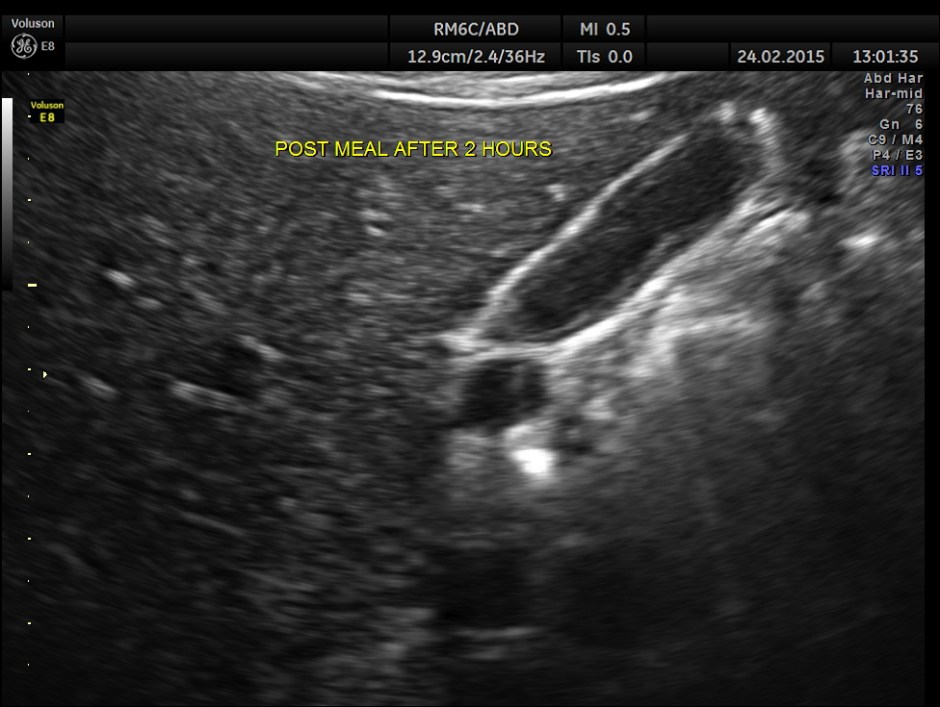

2 hours after the meal the gall bladder was still distended and no gallstone was visualised .

This patient probably had a functional gall bladder abnormality , asymptomatic at present.

Contrary to expectations she had a collapsed gall bladder in the fasting status and a partial filling up of bile after a fatty meal. As she had no symptoms , she was advised periodic follow up once in 6 months to start with.